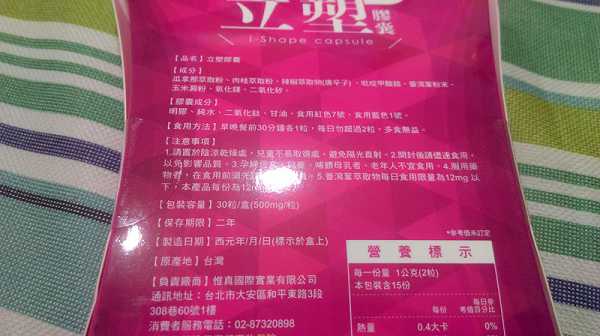

Supercut塑魔纖立塑膠囊的成分有:瓜拿那萃取粉、肉桂萃取粉、辣椒萃取物(唐辛子)、吡啶甲酸鉻、番瀉葉粉末、玉米澱粉、氧化鎂、二氧化矽。

之前上過相關課程,成分表是依照每項成分的多寡來排列順序,排在最前面的就是產品的主要成分!

那我就跟大家分享瓜拿那萃取粉、肉桂萃取粉和辣椒萃取物吧

瓜拿那萃取和辣椒萃取是可以幫助纖體瘦身常見的營養素!

1.「瓜拿那」是原產於亞馬遜流域的一種藤蔓植物,富含酵素可以幫助排便順暢,並且能抑制脂肪分解酵素,此外也有降低食慾的效果喔~~萃取物中含有天然咖啡因,可以提高新陳代謝率以及排出多餘水分!

2.「辣椒萃取物」則是可以幫助體內脂肪燃燒、增加卡路里的消耗,達到防止脂肪積聚的效果

3.「肉桂萃取物」看到肉桂,就想到麥當勞的蘋果派或是手掌麵包,雖然很多人很害怕那味道,但艾哥愛死肉桂了!!!!肉桂在古代被視為是最有價值的東方香料之ㄧ,中世紀時,肉桂的聲望僅次於昂貴的黑胡椒,除了香料和薰香價值, 傳統上肉也被用來治療消化不良、脹氣、關節疼痛、出血和經痛,研究也指出肉桂可以促進新陳代謝喔

食用方式:早晚餐前30分鐘各1粒,每日不超過2粒。(多食無益)

番瀉葉萃取物每日食用限量為12mg以下,

鉻與脂肪代謝有關,有助於控制血液中的膽固醇,並有降低血壓的作用,可以預防高血壓,對降低體重也有不錯的效果。